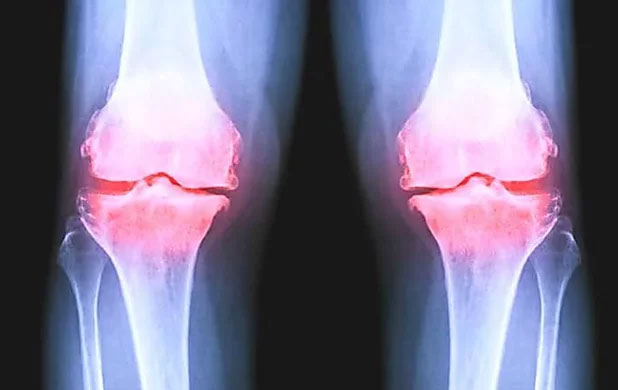

Ik ontdekte een baanbrekend onderzoek van deUniversiteit van Californië gepubliceerd in december 2022 waarin werd onderzocht 277 mensen met een matige tot ernstige kniegewrichtsontsteking die minimaal een jaar lang regelmatig ontstekingsremmende pijnstillers slikten.

De resultaten waren alarmerend: Het nemen van ontstekingsremmende pijnstillers verergerde de symptomen van artrose zelfs in de loop van de tijd!

MRI-onderzoeken wezen dat uit gewrichtsontsteking bij degenen die nemen pijnstillers verergerd aanzienlijk meer dan vier jaar.

Hun kraakbeen is afgebroken veel sneller dan in de vergelijkingsgroep die geen pijnstillers slikte.